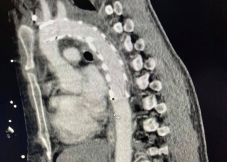

életmentő műtét